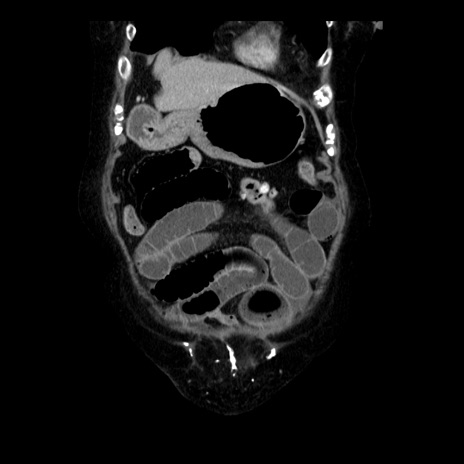

症例14(冠状断像)

【症例】 90歳代女性

【主訴】 腹痛・嘔吐

【現病歴】今朝から左側腹部痛を認めた。 経過観察していたが、嘔吐を認めたため来院。

【既往歴】 子宮癌術後

【身体所見】 意識清明、BP 127/54mmHg、P 98bpm Sp02 95%(RA)、BT 35.8°C、腹部平坦・軟腸ぜん動音聴取良好、右下腹部圧痛(+) 反跳痛なし

【データ】WBC 9800、CRP 0.46